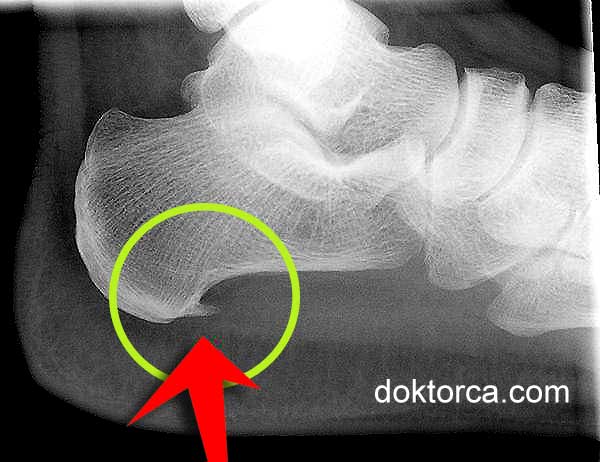

Topuk dikeni topuğun alt kısmında oluşan ve yüksek oranda kalsiyum içeren kemik uzantısıdır. Ayak röntgen grafisinde (X-ray) adeta büyük bir dikeni andıran görüntüden dolayı da “Topuk Dikeni” olarak bilinir.

Latincede Calcaneal Spur, Kalkaneal Spur, Calcaneal Epin denir. Bazen bu durum röntgende görülmez ve “Topuk Dikeni Sendromu” olarak adlandırılır.

Kalsiyumun topuk kemiği üzerinde tortu ve katmanlar halinde birikimi ve topuk dikeni şeklinde kemiksi uzantı oluşturması uzun zaman gerektirir, çoğu zaman yıllar bazen de aylar. Topuk kısmında dikenin oluşmasında rol oynayan faktörler arasında ise: